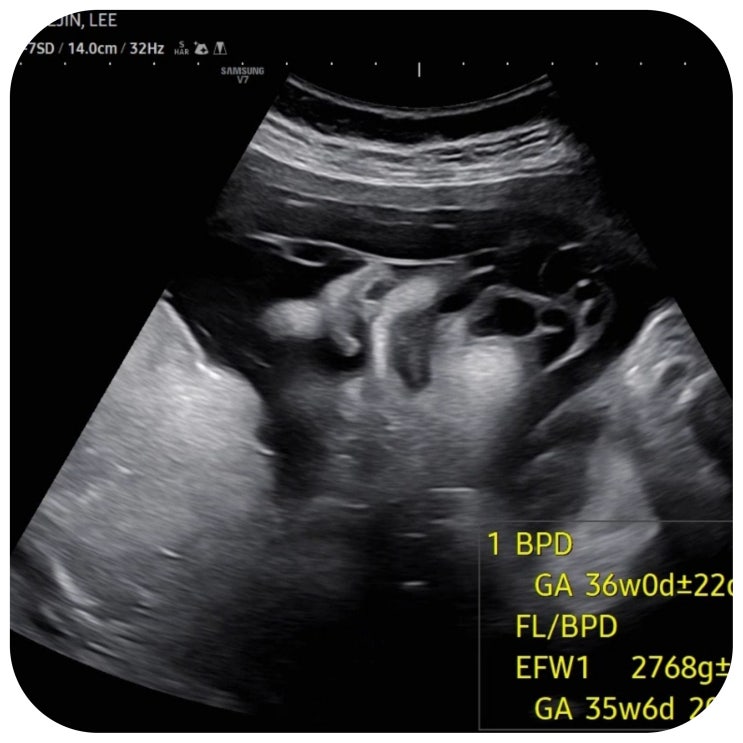

임신37주1일 덕천 미래로 출산 전 마지막 정기진료! 제왕절개 분만 안내

제왕절개 날까지 D-7일이에요! 지난주 토요일에 정기 외래진료받았고 수술 전까지 한 번의 외래진료가 남...